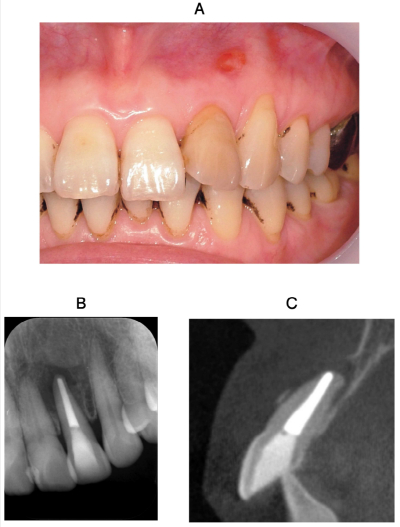

72歳の女性。上顎左側側切歯の歯肉の異常を主訴として来院した。6か月前に根管治療を受けたという。打診痛と根尖部歯肉圧痛を認め、プロービングデプスは全周2mmであった。初診時の口腔内写真、エックス線写真及び追加撮影した歯科用コーンビームCTを別に示す。

歯科用コーンビームCTで新たに得られた所見はどれか。2つ選べ。

a. 管外側枝

b. 歯根破折

c. 根尖部穿刺

d. 皮質骨断裂

e. セメント質剝離